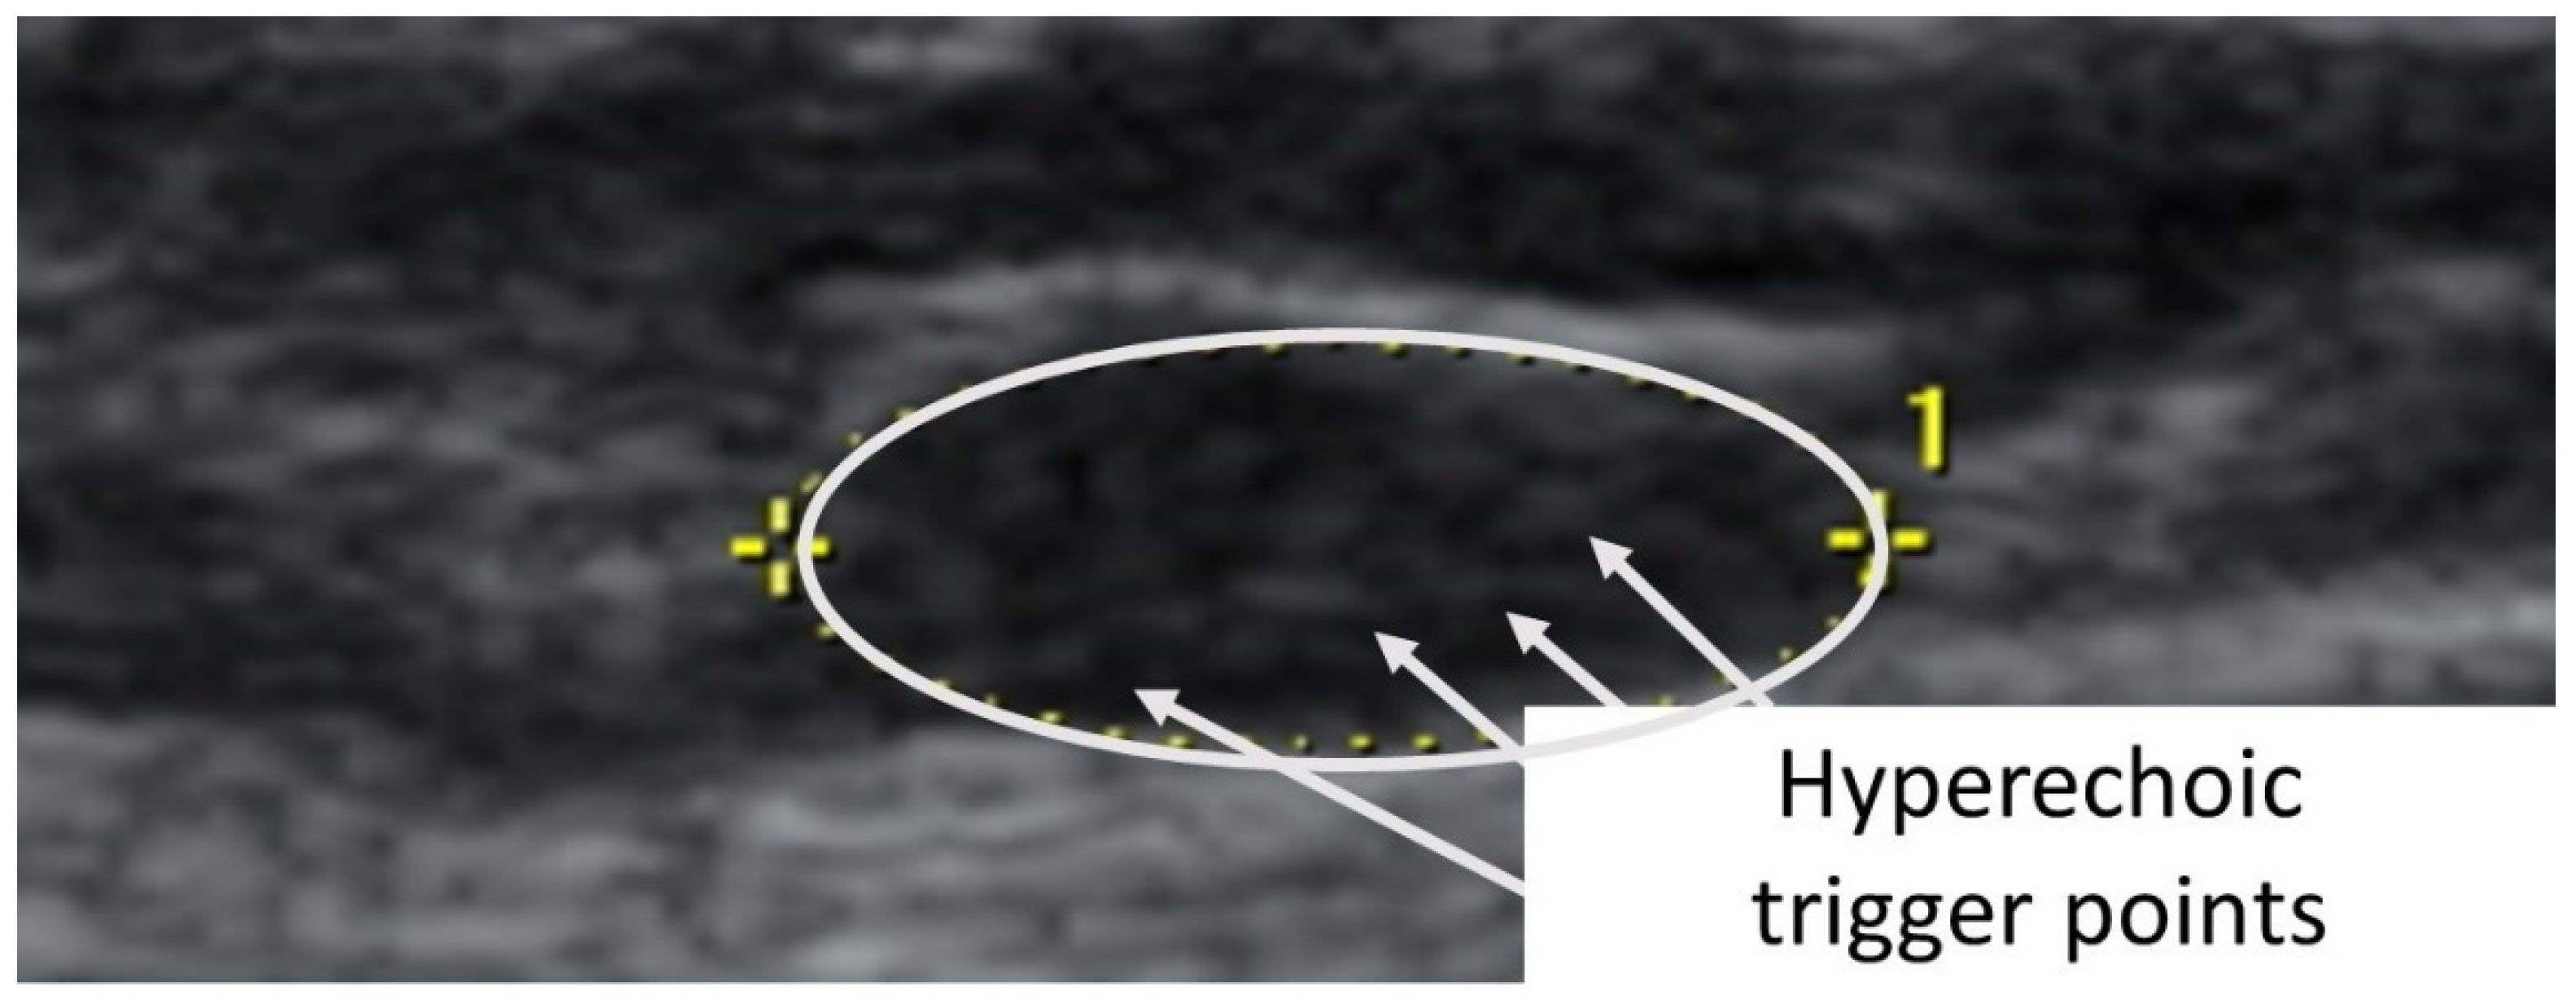

A taut band with a palpable nodule within the medial gastrocnemius was identified as responsible for his right plantar heel pain symptoms [32]. As had been the case with previous bouts of plantar pain, the subject reported, upon palpation, a pain referral symptomatology into the plantar aspect of his foot as his pain symptoms (pain recognition). The nodule was subsequently imaged in long-axis with a Siemens Acuson S200 Ultrasound system (Siemens, Munich, Germany) with an 18L6 16 Hz high-definition linear probe. A large hypoechoic contracture knot (109 mm × 47 mm) was identified (Figure 1) with smaller hyperechoic “speckles” (Figure 2) within the hypoechoic contracture knot.

Figure 2.

Detailed ultrasound imaging assessment of the right gastrocnemius muscle showing a collection of small hyperechoic (hypoperfused) “TrP speckles” within the contracture knot.

Considering that the pathogenesis of TrPs consists of dysfunctional motor endplates and they are ischemic areas in nature, previous studies may have mislabeled contracture knots as TrPs [19]. In each case presented, a hypoechoic/hyperperfused area of approximately 1 cm × 1 cm was visualized in the vicinity of the palpable nodule, with small hyperechoic/nonpalpable speckles of approximately 1 mm × 1 mm within each. Consistent with the multiple loci hypothesis presented by Hong and Simons [25], we suggest that the relatively large hypoechoic structures visualized as the TrP area in both subjects examined represent hyperperfused contracture knots with smaller, not previously distinguished, ischemic and hyperechoic TrPs within each.